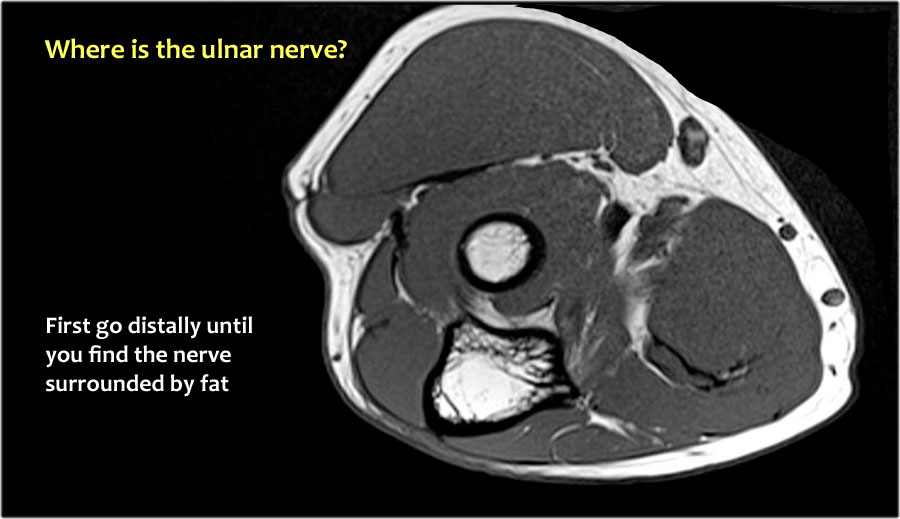

Vì vậy, khi chúng ta quay lại hình ảnh, bạn sẽ nhận thấy rằng có thể khó tìm thấy dây thần kinh.

Bất kỳ cấu trúc dưới da nào trong số này đều có thể là dây thần kinh đã được chuyển vị.

Một cách để thực hiện là đi theo các cấu trúc về phía xa cho đến khi tìm thấy dây thần kinh trụ ở phía xa tại vị trí bình thường của nó ở vùng cẳng tay gần được bao quanh bởi mô mỡ.

Sau đó khi bạn theo dõi nó về phía gần, bạn sẽ nhận thấy rằng đây là một trường hợp chuyển vị dưới da.